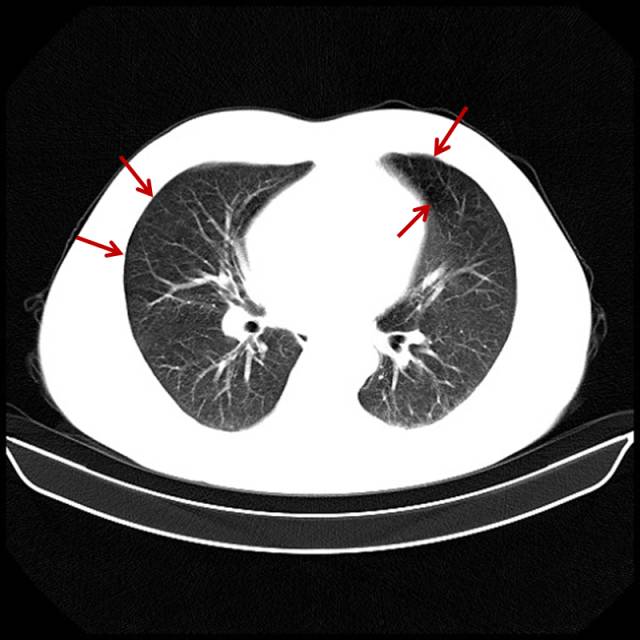

吸烟导致的中重度肺气肿

男,65岁,咳嗽、气短、吸烟几十年。

图片

图7

双肺多个小无肺纹区。有自觉症状,患者基本会意识到气短与吸烟有关。此类患者戒烟不戒烟,完全取决于自己的毅力。相当一部分患者已经成瘾,或者说成习惯了,会说慢慢戒、减量。我见过一天最多能吸5盒烟的。